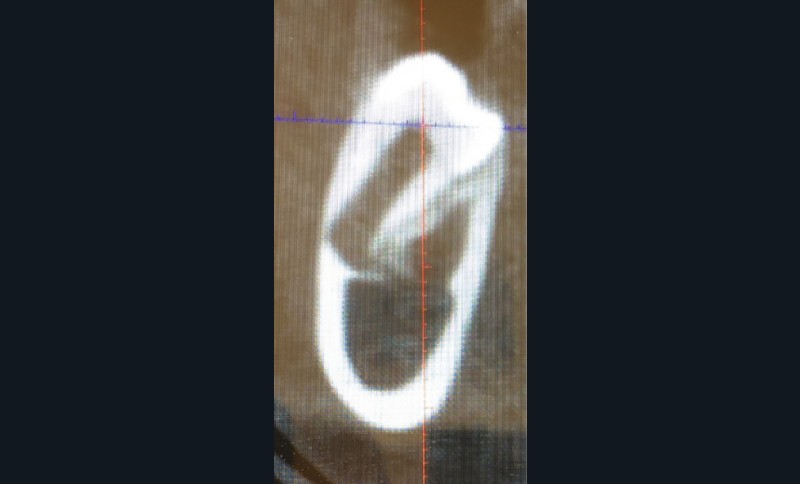

Un bilan radiologique 3D (Cone Beam CT) est prescrit dans le but d’évaluer, avec l’équipe de chirurgie du Dr Jean-Luc Charrier (Hôpital Bretonneau), la possibilité de transplantation d’une prémolaire du secteur 4 vers le secteur 1 et de définir le meilleur transplant possible entre 44 et 45. Sont analysées les dimensions du site receveur ainsi que l’anatomie, la position et l’état de maturation radiculaire des prémolaires candidates à la transplantation (fig. 3).

- Concernant 45 :

- sa situation endo-osseuse (à l’abri de la flore bactérienne buccale et avec un desmodonte immature car non soumis aux stimuli occlusaux, facilitant une avulsion atraumatique) et son immaturité radiculaire franche (apex largement ouvert favorisant la revascularisation) font d’elle un transplant de choix ;

- mais il existe une proximité nette entre la couronne de 45 et la racine de 44, (augmentant le risque de lésion de 44 lors de l’avulsion de 45), et un rapport étroit entre la couronne de 45 et la corticale osseuse vestibulaire (augmentant le risque de lésion parodontale post-extractionnelle) ;

- enfin, 45 présente une longueur radiculaire encore courte risquant d’amener à un rapport couronne/racine limite in fine si l’édification radiculaire devait être stoppée après la transplantation de cette dent ;